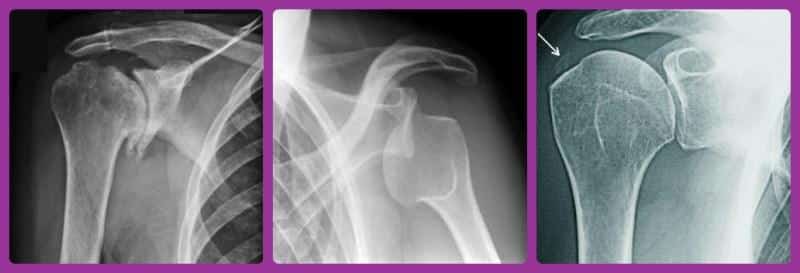

Рентгенография активно используется для диагностики состояния плечевого сустава, так как это один из самых доступных, быстрых и информативных способов выявления различных нарушений.

Рентген плечевого сустава (фото смотрите ниже в разделе) назначается в следующих ситуациях:

- Подозрение на вывих, подвывих, перелом костей плеча, а также повреждение лопатки или ключицы.

После выполнения рентгенологического исследования врач-рентгенолог получает черно-белые изображения и начинает их анализировать.

Что можно увидеть на рентгене плечевого сустава?Полученные снимки позволяют специалисту оценить состояние костной ткани и сустава, а также выявить наличие патологий:

- повреждения костной ткани (переломы, трещины), которые на изображениях выглядят как просветы;

- форму и структуру костной ткани, включая наличие острых краев и наростов;

- изменения и деформации в хрящевой ткани;

- аномальное разрастание костной ткани, связанное с обменными нарушениями в организме;

- положение суставных поверхностей относительно друг друга (вывихи, подвывихи);

- врожденные аномалии развития плечевого сустава;

- изменения и сужение суставной щели;

- уплотнение субхондральной кости и капсулы;

- наличие внутрисуставных отеков, воспалительной жидкости или гнойных образований (на снимках это проявляется затемнениями).